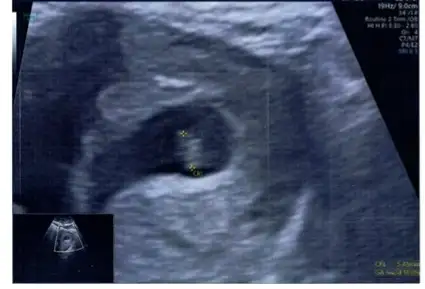

Kızlar herkese selam ! 8 haftalık gebeyim ve hemen hemen her anne adayı gibi cinsiyetini aşırı merak ediyorum. Tabikide önceliğim sağlıklı olması bunu söylemeye bile gerek yok, bizimki biraz olayım heyecanı :) Ramzi teorisi diye bir şey gördüm konudan anlayan ekteki ultrasonda fotoğrafıma göre cinsiyetiyle ilgili tahminde bulunabilir mi acaba?

Cinsiyeti nedir acaba 😍